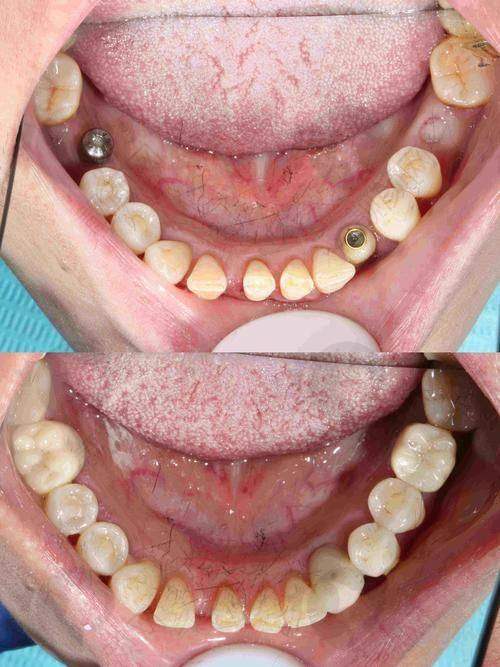

上海鼎植许士强全口半口种植实例

曾有一位老年患者,全口牙齿缺失多年,生活受到了极大的影响。患者来到上海鼎植口腔找到许士强医生,希望能够解决牙齿缺失的问题。许医生经过详细的检查和评估,为患者制定了全口半口种植方案。在手术过程中,许医生凭借不错的技术和丰富的经验,顺利完成了种植手术。术后,患者修复良好,牙齿功能得到了极大的改善,生活质量也得到了显著提高。患者对许医生的技术和服务非常满意,称赞他是一位医术高超、职责心强的好医生。